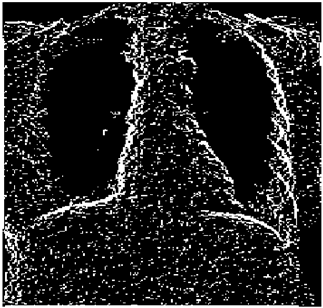

Table 5. X-ray Images.

X-ray 1X-ray 2X-ray 3X-ray 4X-ray 5

Mathematics 10 02421 i004 Mathematics 10 02421 i005 Mathematics 10 02421 i006 Mathematics 10 02421 i007 Mathematics 10 02421 i008

For the purpose of simulation, we consider two sets of images: (1) three images from MATLAB repository (Table 4) and (2) five X-ray images available online (Table 5).

Table 10 shows the following:

• In all cases, the Canny edge detector detects more edge pixels than both fuzzy compositions.

• As the level of noise increases, Canny and standard composition become adversely affected by the noise, and still more edges are detected by Canny; however, most of the detected edges by Canny are misdetections due to the impact of noise. As is obvious from this table, the smooth composition provides a better image with reduced noise density.

• In all cases, the PFOM value for the smooth composition is always greater than the PFOM value for the standard composition, according to Table 6.